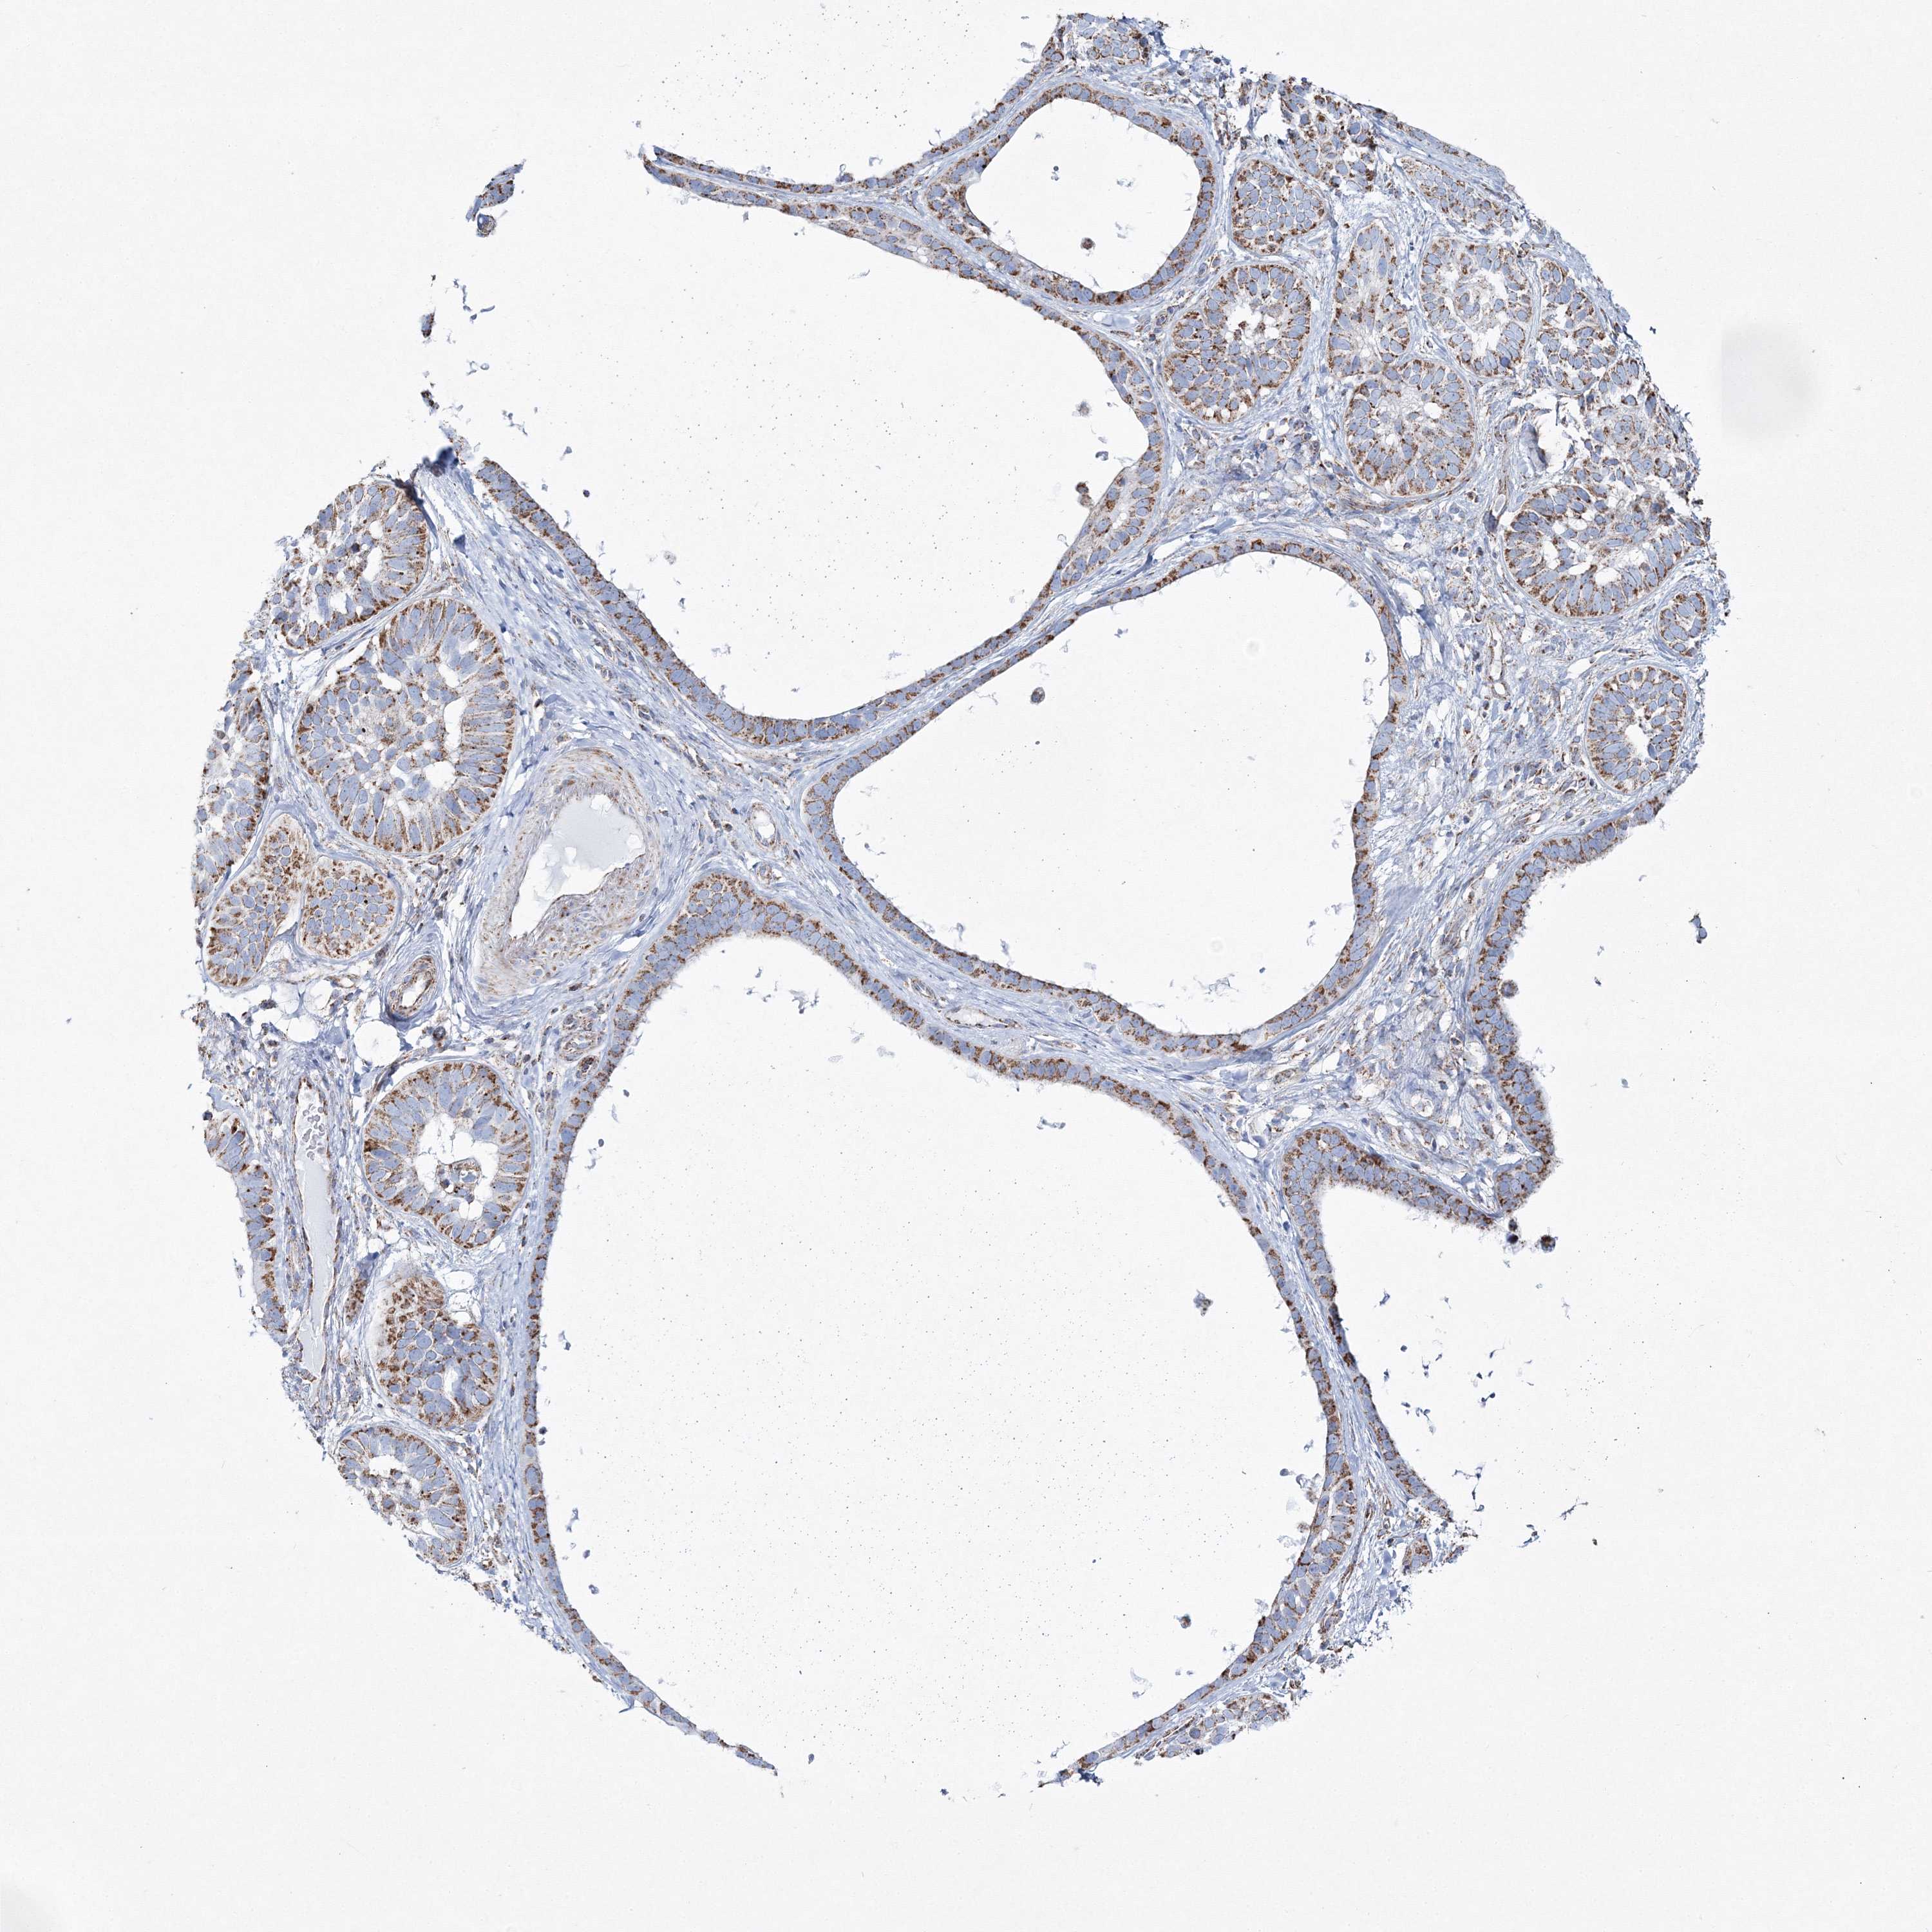

Basal cell and squamous cell cancer

SKIN CANCER - Protein expressioni

A mouse-over function shows sample information and annotation data. Click on an image to view it in a full screen mode. Samples can be filtered based on level of antibody staining by selecting one or several of the following categories: high, medium, low and not detected. The assay and annotation is described here.

Antibody stainingi

Antibody staining in the annotated cell types in the current human tissue is reported as not detected, low, medium, or high, based on conventional immunohistochemistry profiling in selected tissues. This score is based on the combination of the staining intensity and fraction of stained cells.

Each image is clickable and will lead to virtual microscopy that enables deeper exploration of all samples and also displays staining intensity scores, fraction scores and subcellular localization as well as patient and tissue information for each sample.

Antibody HPA036540

Antibody HPA036541

Staining

High

Medium

Low

Not detected

Intensity

Strong

Moderate

Weak

Negative

Quantity

>75%

75%-25%

<25%

None

Location

Nuclear

Cytoplasmic/membranous

Cytoplasmic/membranous,nuclear

Basal cell carcinoma

Squamous cell carcinoma, NOS

Squamous cell carcinoma, metastatic, NOS